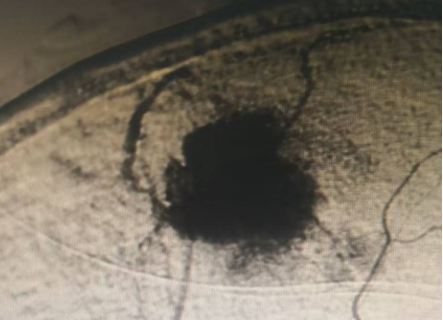

神经外科血管介入组曲友直副教授、崔刚副教授和高攀主治医师对肿瘤进行了瘤栓塞治疗,有效减少了肿瘤的血供,为后续的手术切除降低了风险。栓塞治疗后,神经外科王睿智副主任、高李贵副教授和董全主治医师在麻醉科、心内科、输血科等科室的全力配合下,凭借精湛的医术和丰富的临床经验,成功为患者切除了病变。手术过程中,麻醉科吕建瑞主任团队全程监控患者的生命体征,确保麻醉安全;心内科团队随时准备应对可能出现的心脏问题;输血科团队则确保充足的血液供应,以备不时之需。多学科的通力合作,为手术的成功提供了坚实的保障。